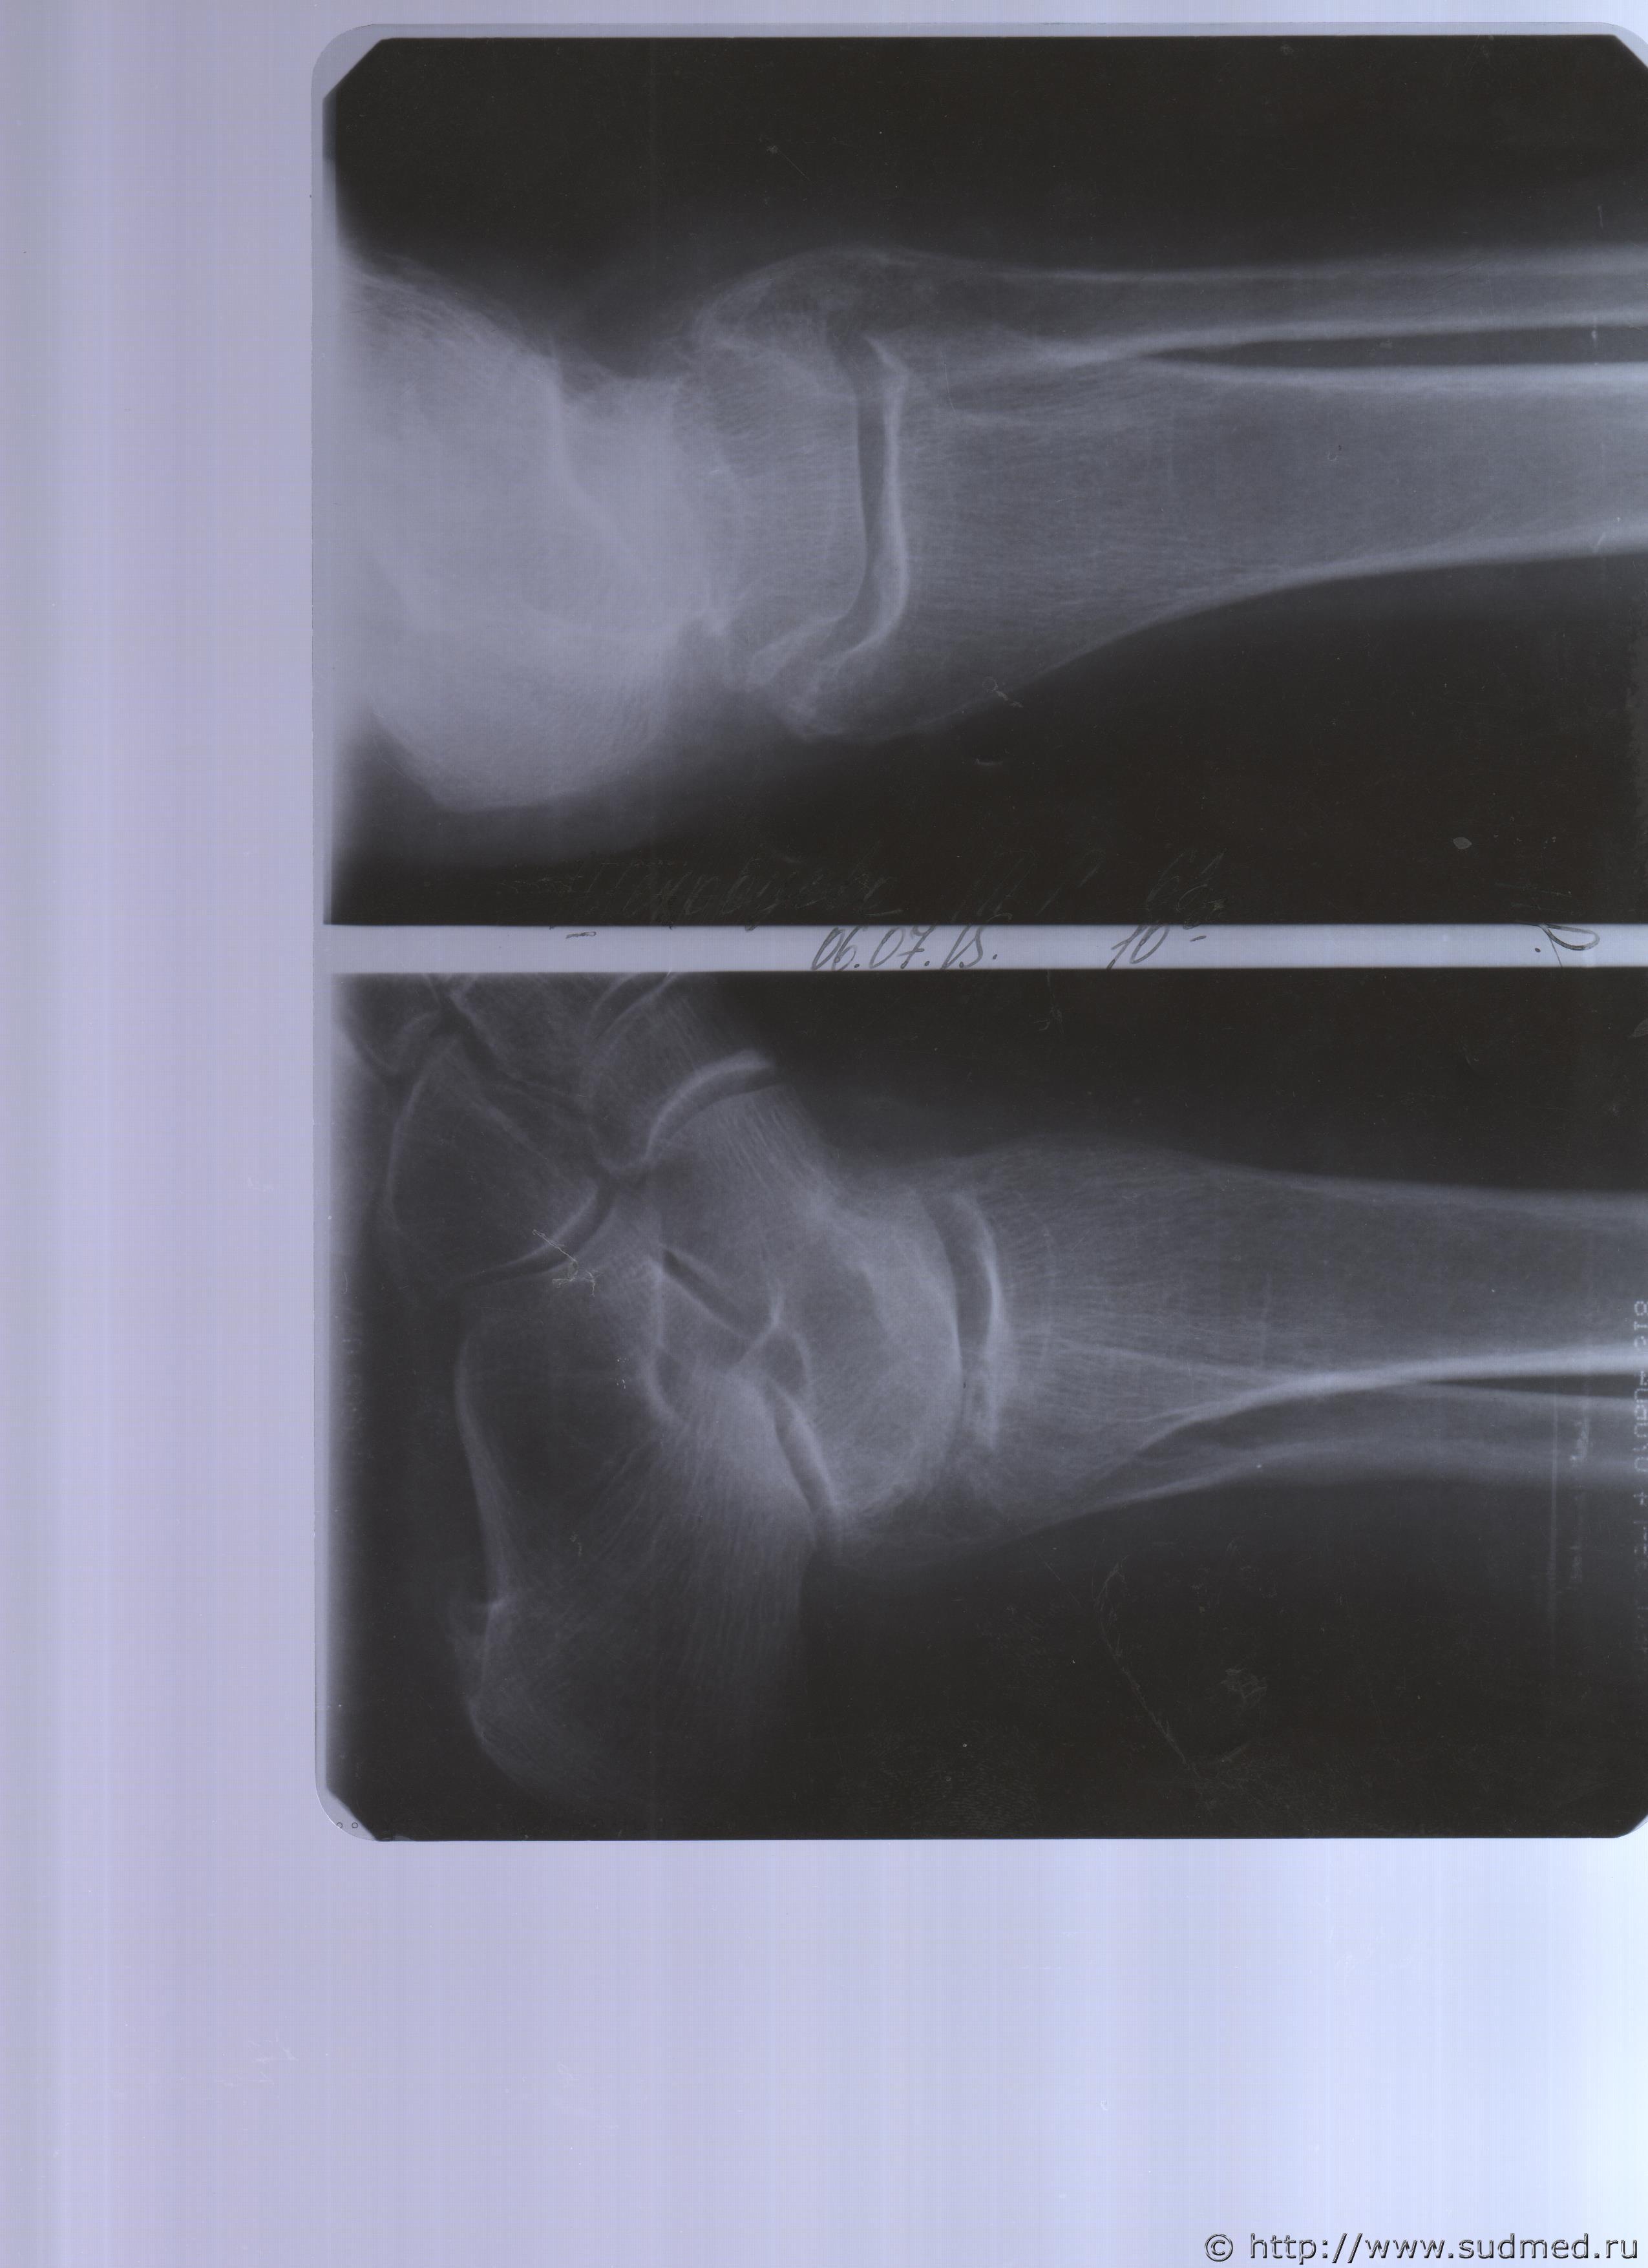

06.07.2015 г. при обращении в горбольницу мне выдали не описанный снимок( все рентгенологи были в отпуске) и справку № 4379 от 06.07.15 г. где диагноз: закрытый 2-х лодыжечный перелом правой голени без смещения. Копию справки прилагаю

За все 12 месяцев, что была на больничном, 8 раз делали снимки травмированной ноги и все заключения именно : «закрытый 2-х лодыжечный перелом правой голени без смещения».

Посмотрите, это снимки за 12 месяцев.

Эскизы прикрепленных изображений

Уважаемая Татьяна! По представленным Вами снимкам ничего сказать нельзя: нет маркировки даты каждого снимка (поэтому, невозможно их сравнивать друг с другом и соотносить с датой травмы), исследование непосредственно пленок гораздо более информативно, чем анализ представленных изображений (детали костной структуры в зоне перелома практически не видны).

Рекомендую проконсультировать все эти снимки у высококвалифицированного рентгенолога. Далее - по ситуации, т.е. в зависимости от его мнения. В любом случае, есть формальные основания для назначения дополнительной экспертизы, т.к., судя по представленному Вами фрагменту заключения эксперта, на экспертизу не были предоставлены все мед.документы с данными о лечении предъявляемой травмы (Вы пишете, что рентгенограммы делались на протяжении 12 месяцев, полагаю, что Вы и врачами наблюдались в течение этого срока, т.е. велась мед.карта).